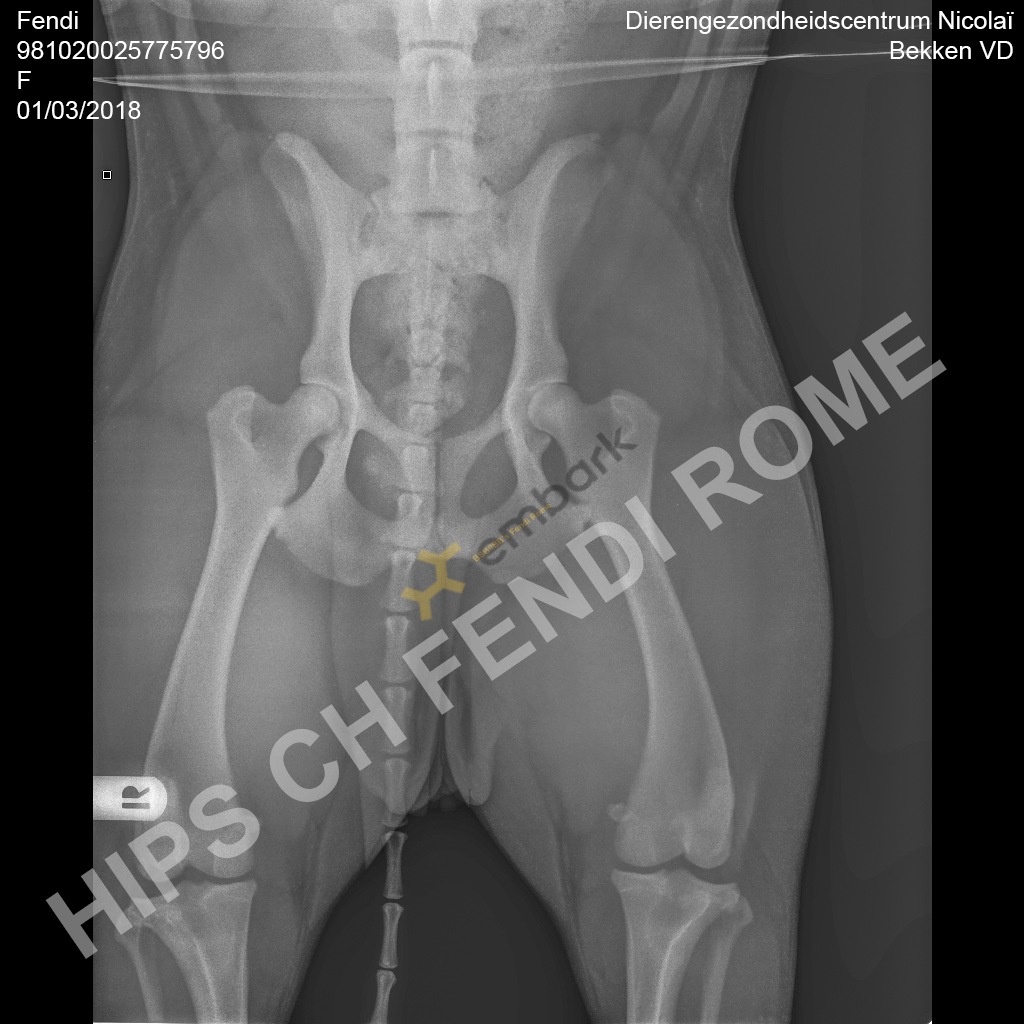

BSB/IBB’s Fendi Rome